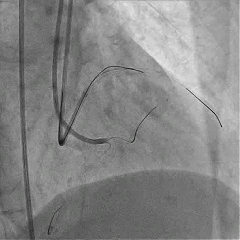

对角支送入IVUS导管,在IVUS实时指引下用尝试穿刺闭塞段

导丝未能进入闭塞段,导丝进入间隔支

逆向造影指引下继续尝试穿刺闭塞段

导丝远端与逆向造影不重叠,未在血管真腔

反复调整导丝最终进入D2#,可见导丝远端与D2侧枝重叠,证明远端位于真腔

微导管交换工作导丝至D2#远端

双腔微导管辅助下,导丝在逆向造影指引下成功通过LAD闭塞段,逆向造影显示导丝走行于LAD真腔内